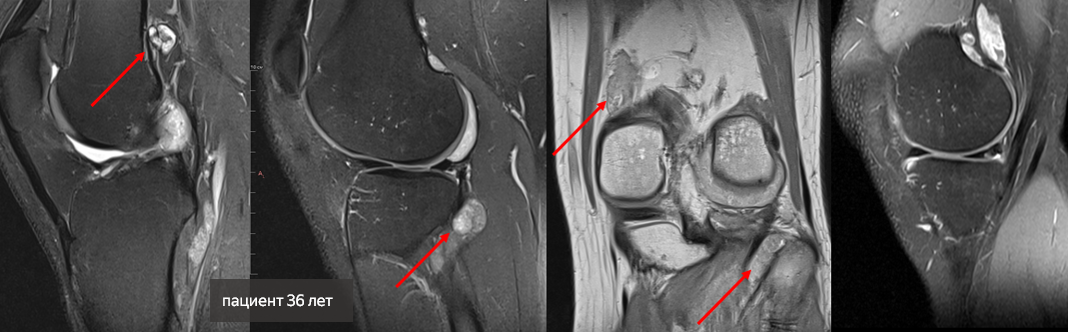

Молодой пациент обратился с жалобами на боли в коленном суставе и нарушение функции. Магнитно-резонансная томография показала наличие в коленном суставе множественных образований.

Рентгенологи поставили знак вопроса относительно точного диагноза 36-летнему мужчине: синовиальный хондроматоз или синовиальная саркома.